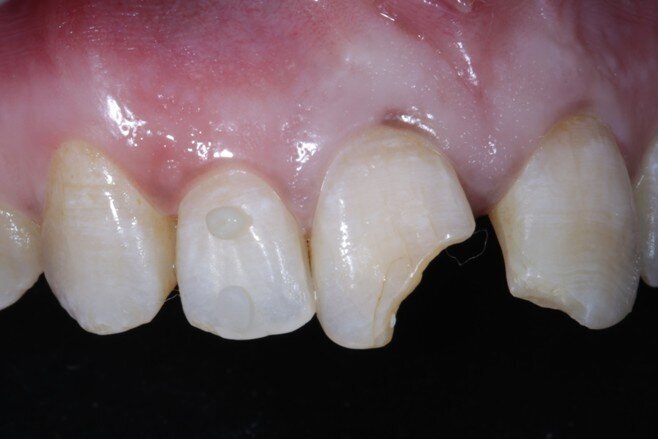

Non-surgical endodontic treatment was done in the 1st week. After the symptoms resolved completely we were ready to restore form, function and aesthetics. Non-vital in-office bleaching was done. Pola office bleach was used for the same, 3 cycles of 8 minutes each. It appeared that the shade had corrected completely after bleaching but we waited for it to stabilize.

Two weeks later, the shade [ Fig 3 ] stabilized and the teeth were ready for bonding. We observed that the central incisors were still darker than the neighboring teeth. Direct composite veneers were planned with the help of a lab made wax up [ Fig 4 ] and a putty index. Bevels were placed and most of the preparation was in enamel. After the total etch protocol, 5th generation bonding agent was used. 3M Z350XT shades were used for the build up. A2 Enamel shade was used for the palatal shell [ Fig 6 ] and the proximal walls [ Fig 11 ].